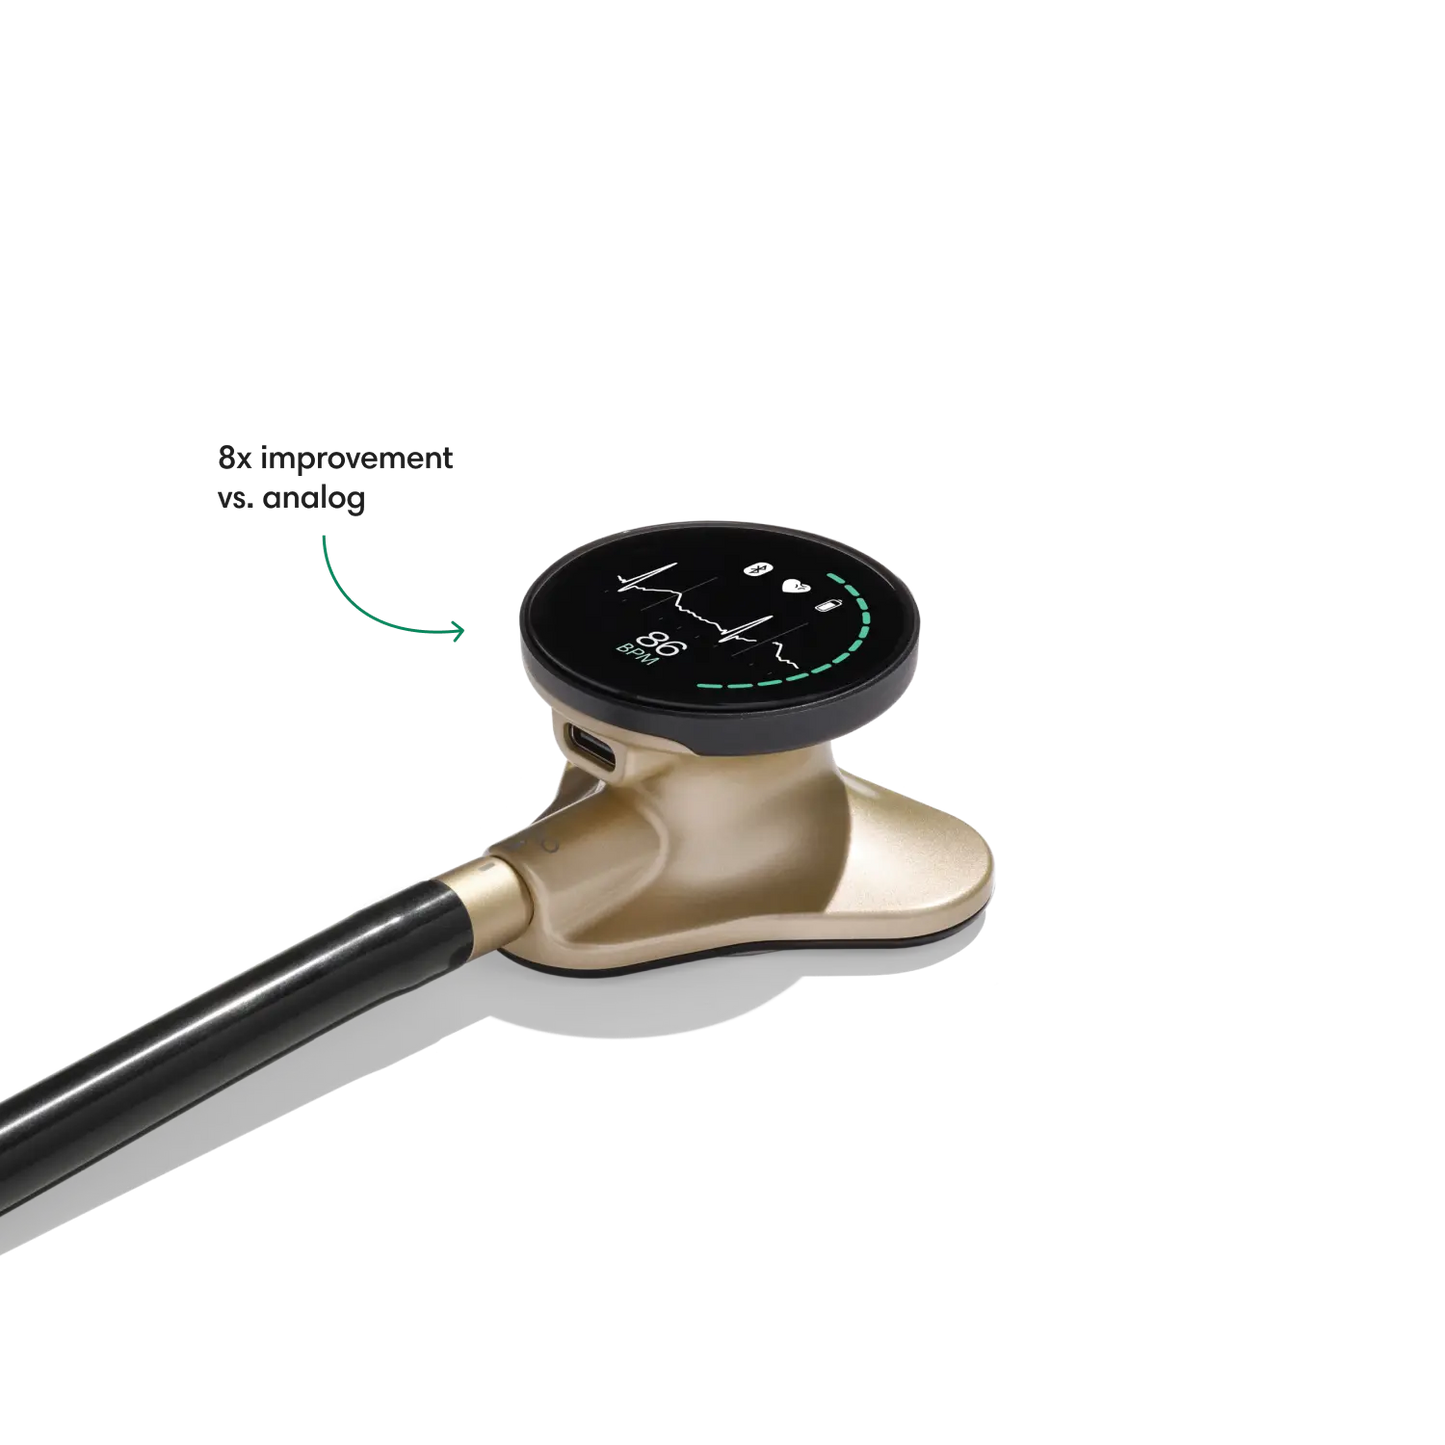

Go beyond sound alone.

For the first time ever, measure heart rate, visualize 3-lead ECG, and see detection results — right on a built-in, full-color display.

- Reduces background noise 8x better vs. a typical analog stethoscope.